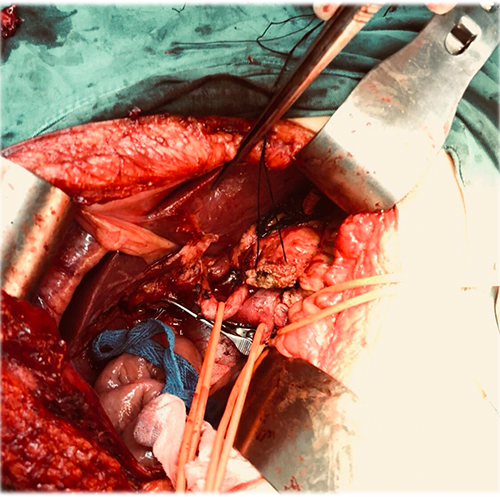

胰头腺癌---胰十二指肠切除